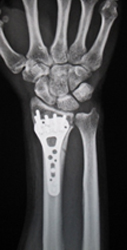

① 橈骨遠位端骨折

粉砕の強い場合、関節内に骨折が及ぶ場合は手術を行います。プレートを用いた整復固定を行いますが、粉砕の強い場合は創外固定や人工骨充填を併用します。